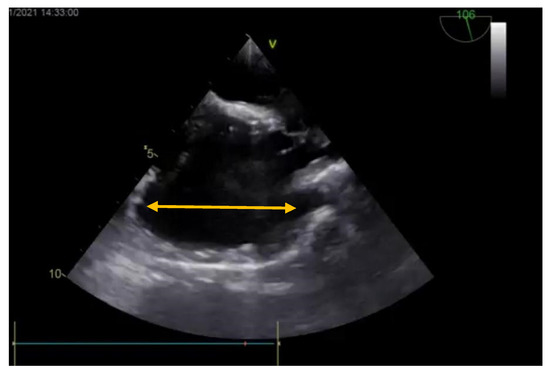

The diagnosis was based on the transthoracic echocardiography (Figure 1 and Figure 2). It revealed an SV-ASD with PAPVD which appeared to open in the right atrium, a dilated right atrium and ventricle, and a left-to-right shunt with Qp:Qs of 2.3 (Qp-pulmonary flow/Qs-systemic flow). The patient had normal pulmonary artery pressure, which was measured during echocardiography.

Figure 2. Preoperative echocardiography (bicaval view) showing the ASD.